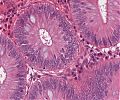

A70 Adenokarzinom des Kolon

Tumordrüsen mit deutlicher Kernpleomorphie

A70 Adenokarzinom des Kolon

Klein- und großdrüsige Tumordifferenzierung an der Invasionsfront